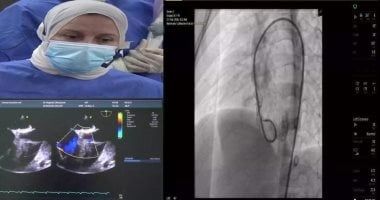

واوضح عميد كلية الطب تفاصيل الحالتين الأولى حالة معقدة لطفل 5 سنوات من محافظة كفر الشيخ يعانى من تضخم بعضلة القلب نتيجة ثقب بين البطين وتم غلق الثقب بنجاح، بينما الحالة الثانية حالة معقدة لطفل 16 سنة من محافظة الغربية تعانى من جلطة سابقة وتم غلق ثقب جنينى بين الأذينين وغادرت الحالتين المستشفى إلى منازلهم فى سلام بعد نجاح منقطع النظير وسط انبهار جميع الحاضرين من المصريين والأجانب بمختلف الجنسيات الذين شاهدوا أحداث البث الحى المباشر وكلا الحالتين ضمن جهود مستشفيات جامعـة طنطا لتنفيذ توجيهات القيادة السياسية فى القضاء على قوائم الانتظار .

والجدير بالذكر أن الفريق الطبي الذى أجرى الحالتين بنجاح يضم، من قسم طب القلب والأوعية الدموية الدكتورة رغدة غنيمى الشيخ أستاذ ورئيس القسم ورئيس وحدة العيوب الخلقية ورئيس المؤتمر و الدكتورة سحر الشدودى و الدكتورة فاطمة أبو السعود طه والدكتورة نوران مصطفى والدكتورة ريم راشد والدكتورة دينا الإبشيهى ومن قسم التخدير والعناية المركزة و الدكتور صبرى أمين أستاذ ورئيس القسم والدكتور عبدالله عرابى والدكتور أحمد زهران والدكتور محمد مصطفى الرفاعى والدكتور أحمد طارق ومن تمريض المستشفيات الجامعية وفنيين الأشعة المتمثل فى محمد الرفاعى وعايدة شرف الدين ومحمد عابد وسعودي أحمد ومعتز حجازى.